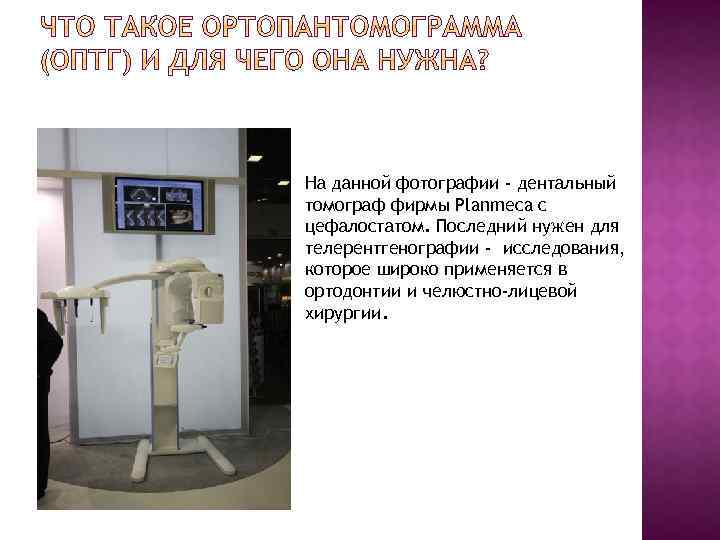

На данной фотографии - дентальный томограф фирмы Planmeca с цефалостатом. Последний нужен для телерентгенографии - исследования, которое широко применяется в ортодонтии и челюстно-лицевой хирургии.